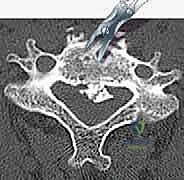

- التصوير المقطعي المحوسب (CT Scan): ضروري جداً لتقييم البنية العظمية، التكلسات (مثل OPLL)، والكسور بدقة ثلاثية الأبعاد.

الخطوة 3: استئصال الأقراص الغضروفية وجسم الفقرة (Corpectomy)

باستخدام الميكروسكوب الجراحي وأدوات دقيقة جداً، يتم أولاً إزالة الأقراص الغضروفية أعلى وأسفل الفقرة المستهدفة. بعد ذلك، يتم استئصال جسم الفقرة العظمي المتضرر بعناية فائقة لفتح مساحة واسعة وتحرير الحبل الشوكي المضغوط.